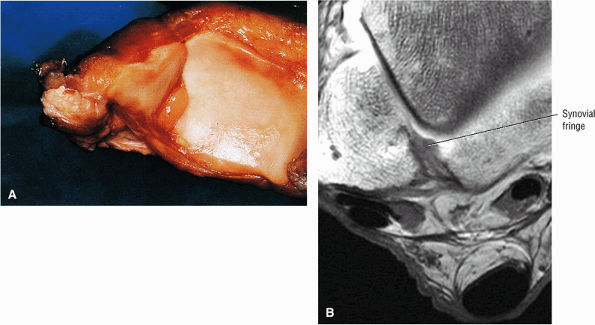

The syndesmotic ligaments consist of the anterior syndesmotic or anterior inferior tibiofibular ligament and the posterior syndesmotic or posterior inferior tibiofibular ligament, the interosseous membrane, and the transverse tibiofibular ligament.

-

The transverse tibiofibular ligament represents the posterior labrum of the ankle and projects inferior to the posterior tibial margin.